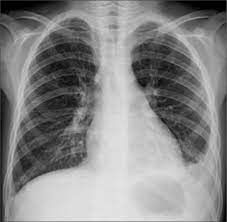

Upload neumo1.jpeg

neumo1.jpeg